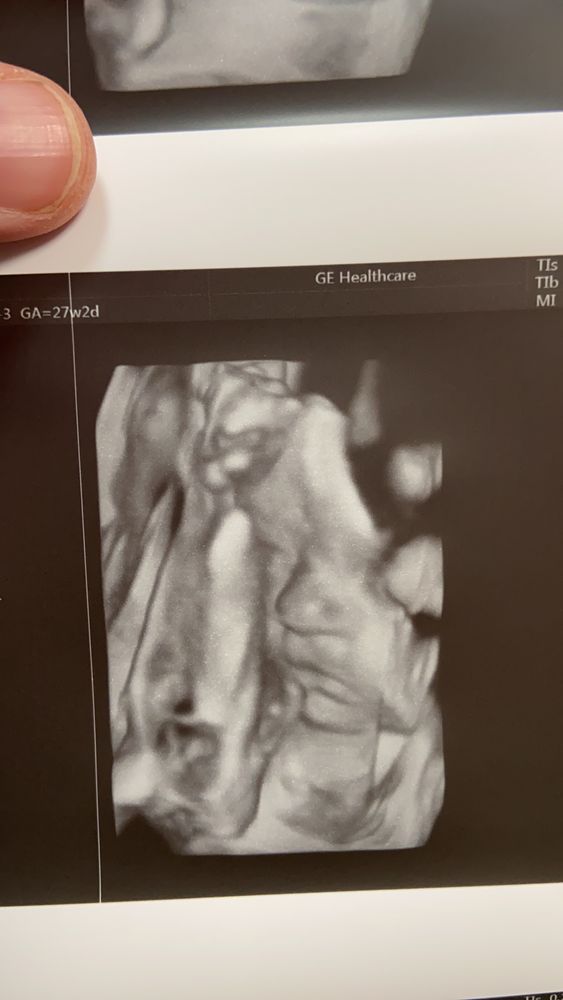

11 февраля 27 недель 2 дня очередное узи с 3д

Все хорошо, малышка подросла, изменилась в лице. Активно зевала и корчила личико. Главное здорова.